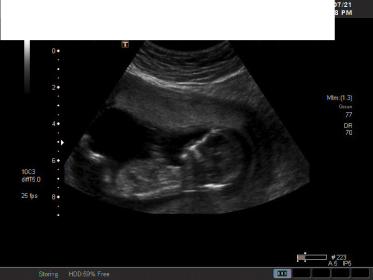

Hi everyone,